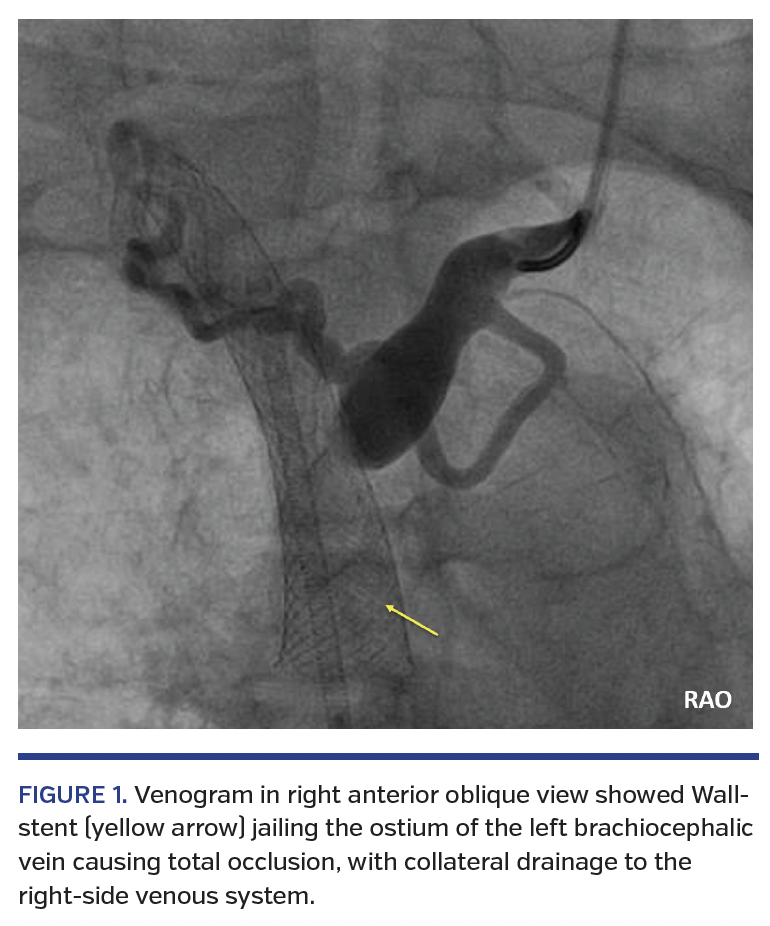

A 60-year-old woman with a history of end-stage renal failure on hemodialysis over right forearm arteriovenous fistula presented with recurrent left arm and facial swelling. She initially presented with facial swelling 2 years ago due to thoracic central vein obstruction (TCVO) secondary to central venous catheter placement. She was treated with balloon angioplasty and implantation of a 16 x 60 mm Wallstent (Boston Scientific) in the superior vena cava (SVC) jailing the left subclavian vein.

In this episode, venography performed via 6 Fr sheath in the left internal jugular vein showed the previous SVC Wallstent jailing the ostium of the left brachiocephalic vein (BCV) causing total occlusion, with collateral drainage to the right-side venous system (Figure 1). An 0.018˝, 30 g Astato chronic total occlusion guidewire (Asahi Intecc) was used to cross the left BCV occlusion through the Wallstent strut into the SVC, snared and externalized through a 9 Fr right common femoral vein sheath to form a “flossing wire.” The Wallstent strut was progressively dilated with a 12 mm Conquest dilation balloon (Bard Peripheral Vascular) up to 20 atm, but there was significant recoil of the stent struts (Figure 2). A 14 x 60 mm, self-expanding, closed-cell, nitinol, dedicated venous Vici stent (Boston Scientific) was deployed in a culotte fashion through the Wallstent strut, landing proximally in the SVC and distally in the left BCV (Figure 3). The stent was postdilated with a 12 mm Conquest balloon. The final result was satisfactory, without significant stent recoil (Figure 4). The patient was given 1 month of clopidogrel. Hemodialysis over her right forearm arteriovenous fistula was smooth afterward. Her arm and facial swelling resolved and remained asymptomatic up to 15 months of follow-up.